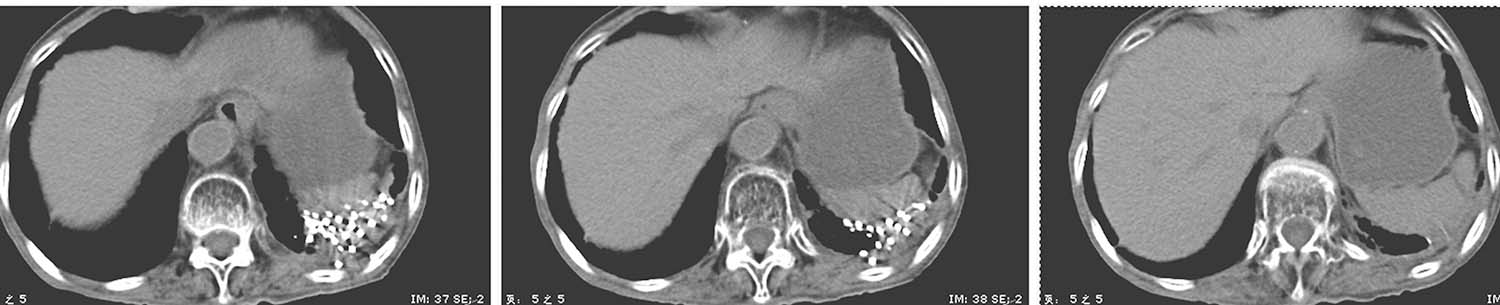

例2 女性,76岁,左肺周围型腺癌,T4N0M0,2017年10月12日行共面模板引导放射性粒子植入术(图4-3-8~图4-3-13)。

图4-3-10 共面模板引导,一次性完成所有层面进针

图4-3-11 术后等剂量分布图

图4-3-12 术后粒子分布三维重建图

图4-3-13 术后7个月复查,病灶明显缩小,疗效部分缓解

(张开贤)